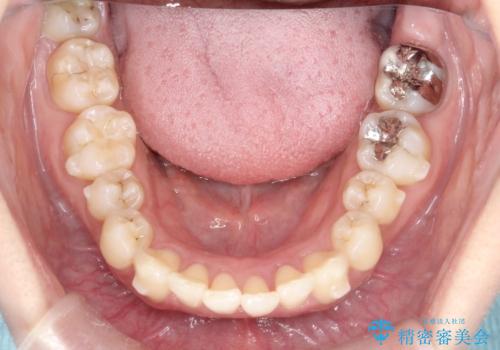

- 前歯のでこぼこが気になると来院されました。

奥歯の噛み合わせは綺麗に噛んでいたため、前歯の叢生(でこぼこ)を、短期間で治療完了するように計画しました。

奥歯の噛み合わせは整っていたため、前歯の並びを美しく修正することに専念できました。マウスピース矯正による治療で短期間で改善しました。